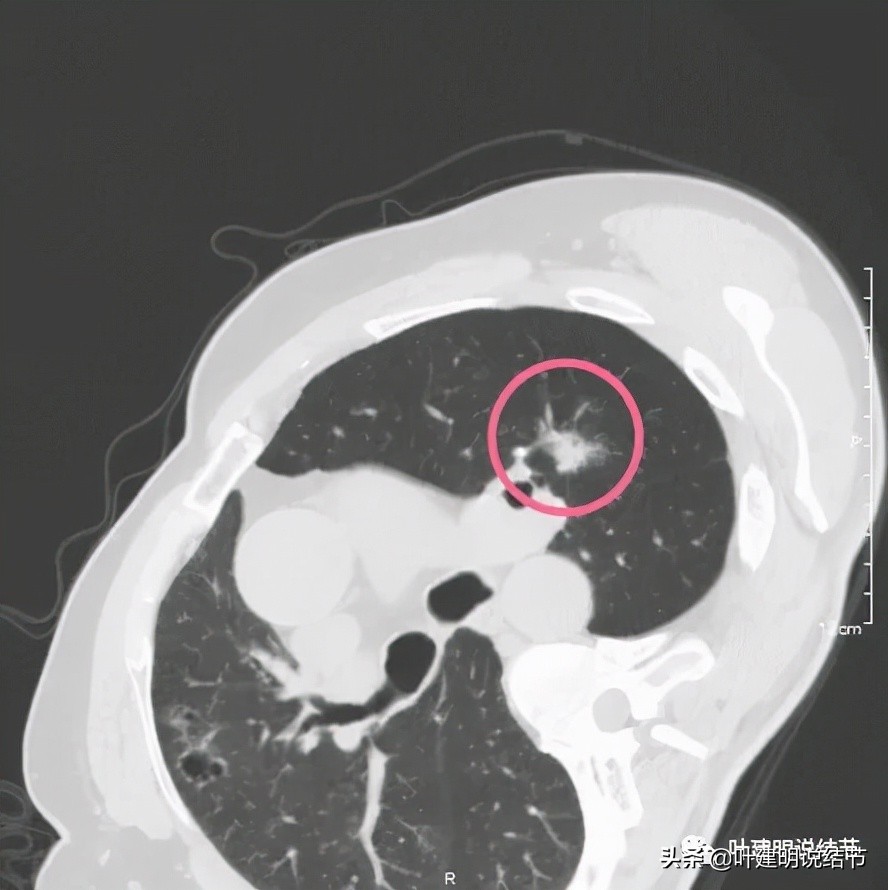

左上主病灶,是混合磨玻璃结节,基本已经都是实性了的,而且位置特别不好,很靠肺门部

左上肺次病灶,磨玻璃结节为主,有少许偏高密度,位置在尖后段